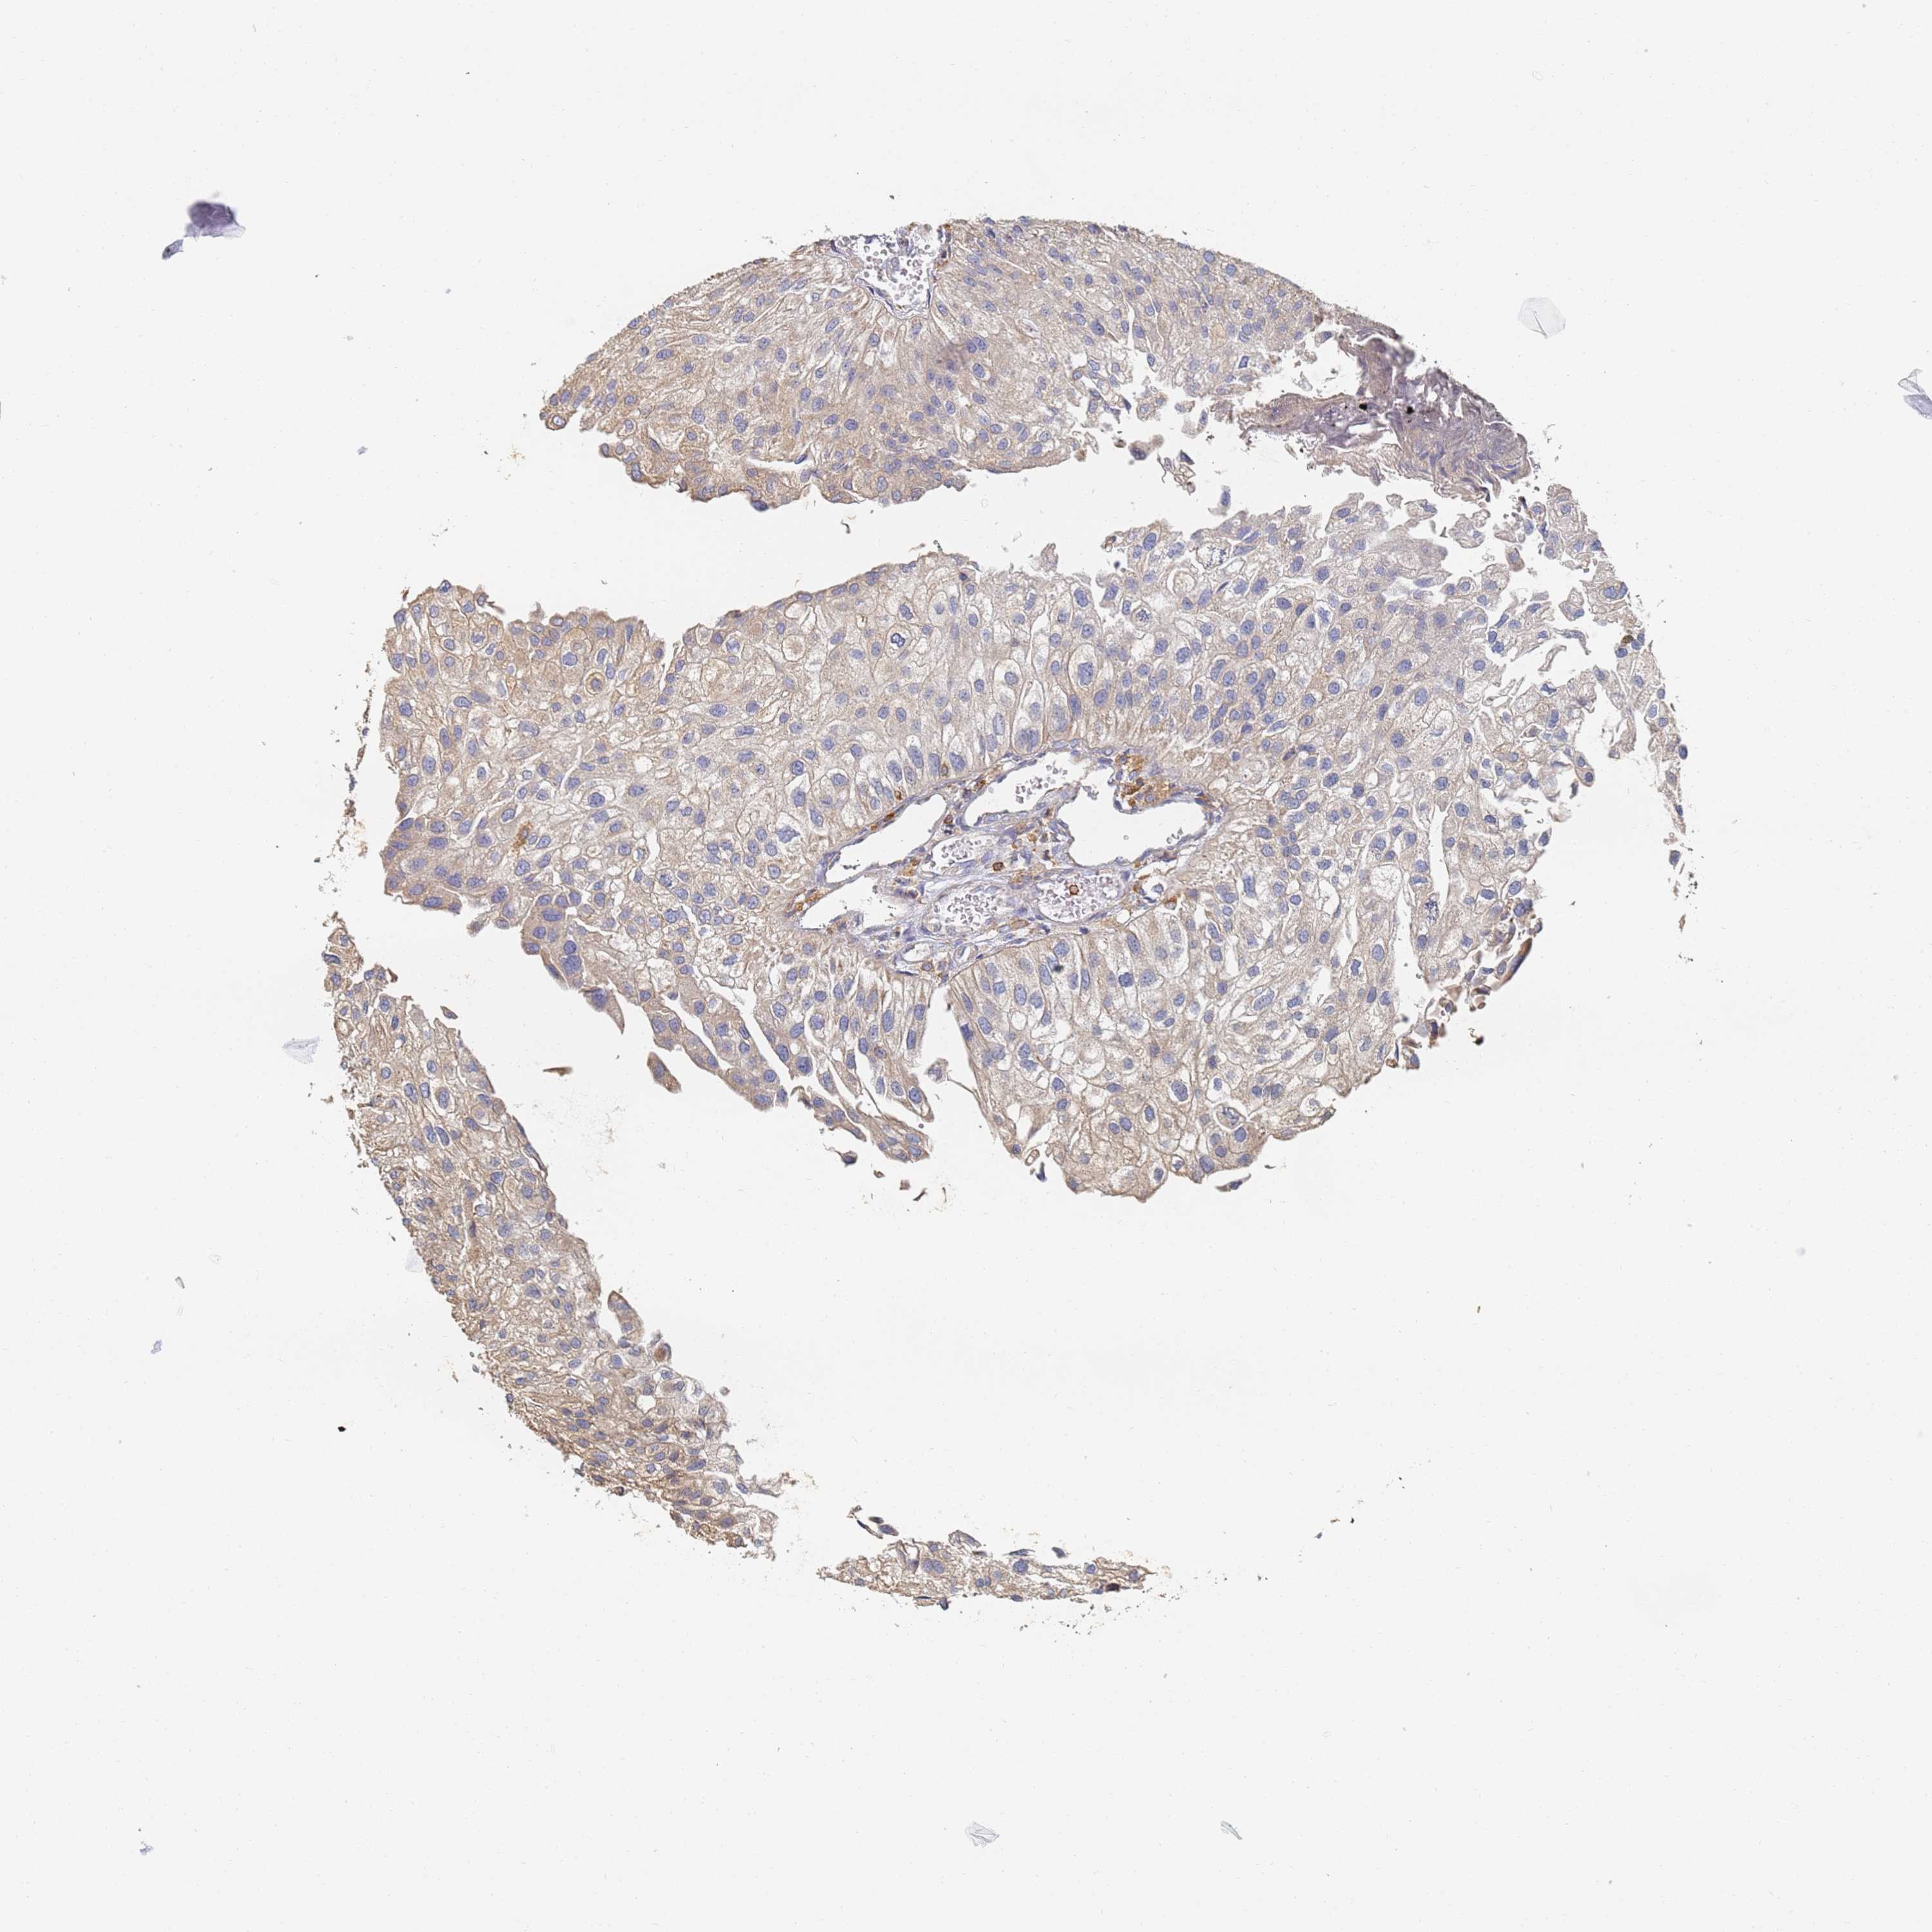

UROTHELIAL CANCER - Protein expressioni

A mouse-over function shows sample information and annotation data. Click on an image to view it in a full screen mode. Samples can be filtered based on level of antibody staining by selecting one or several of the following categories: high, medium, low and not detected. The assay and annotation is described here.

Note that samples used for immunohistochemistry by the Human Protein Atlas do not correspond to samples in the TCGA dataset.

Antibody stainingi

Antibody staining in the annotated cell types in the current human tissue is reported as not detected, low, medium, or high, based on conventional immunohistochemistry profiling in selected tissues. This score is based on the combination of the staining intensity and fraction of stained cells.

Each image is clickable and will lead to virtual microscopy that enables deeper exploration of all samples and also displays staining intensity scores, fraction scores and subcellular localization as well as patient and tissue information for each sample.

Antibody HPA038666

Antibody HPA038667

Urothelial carcinoma, High grade

Urothelial carcinoma, Low grade